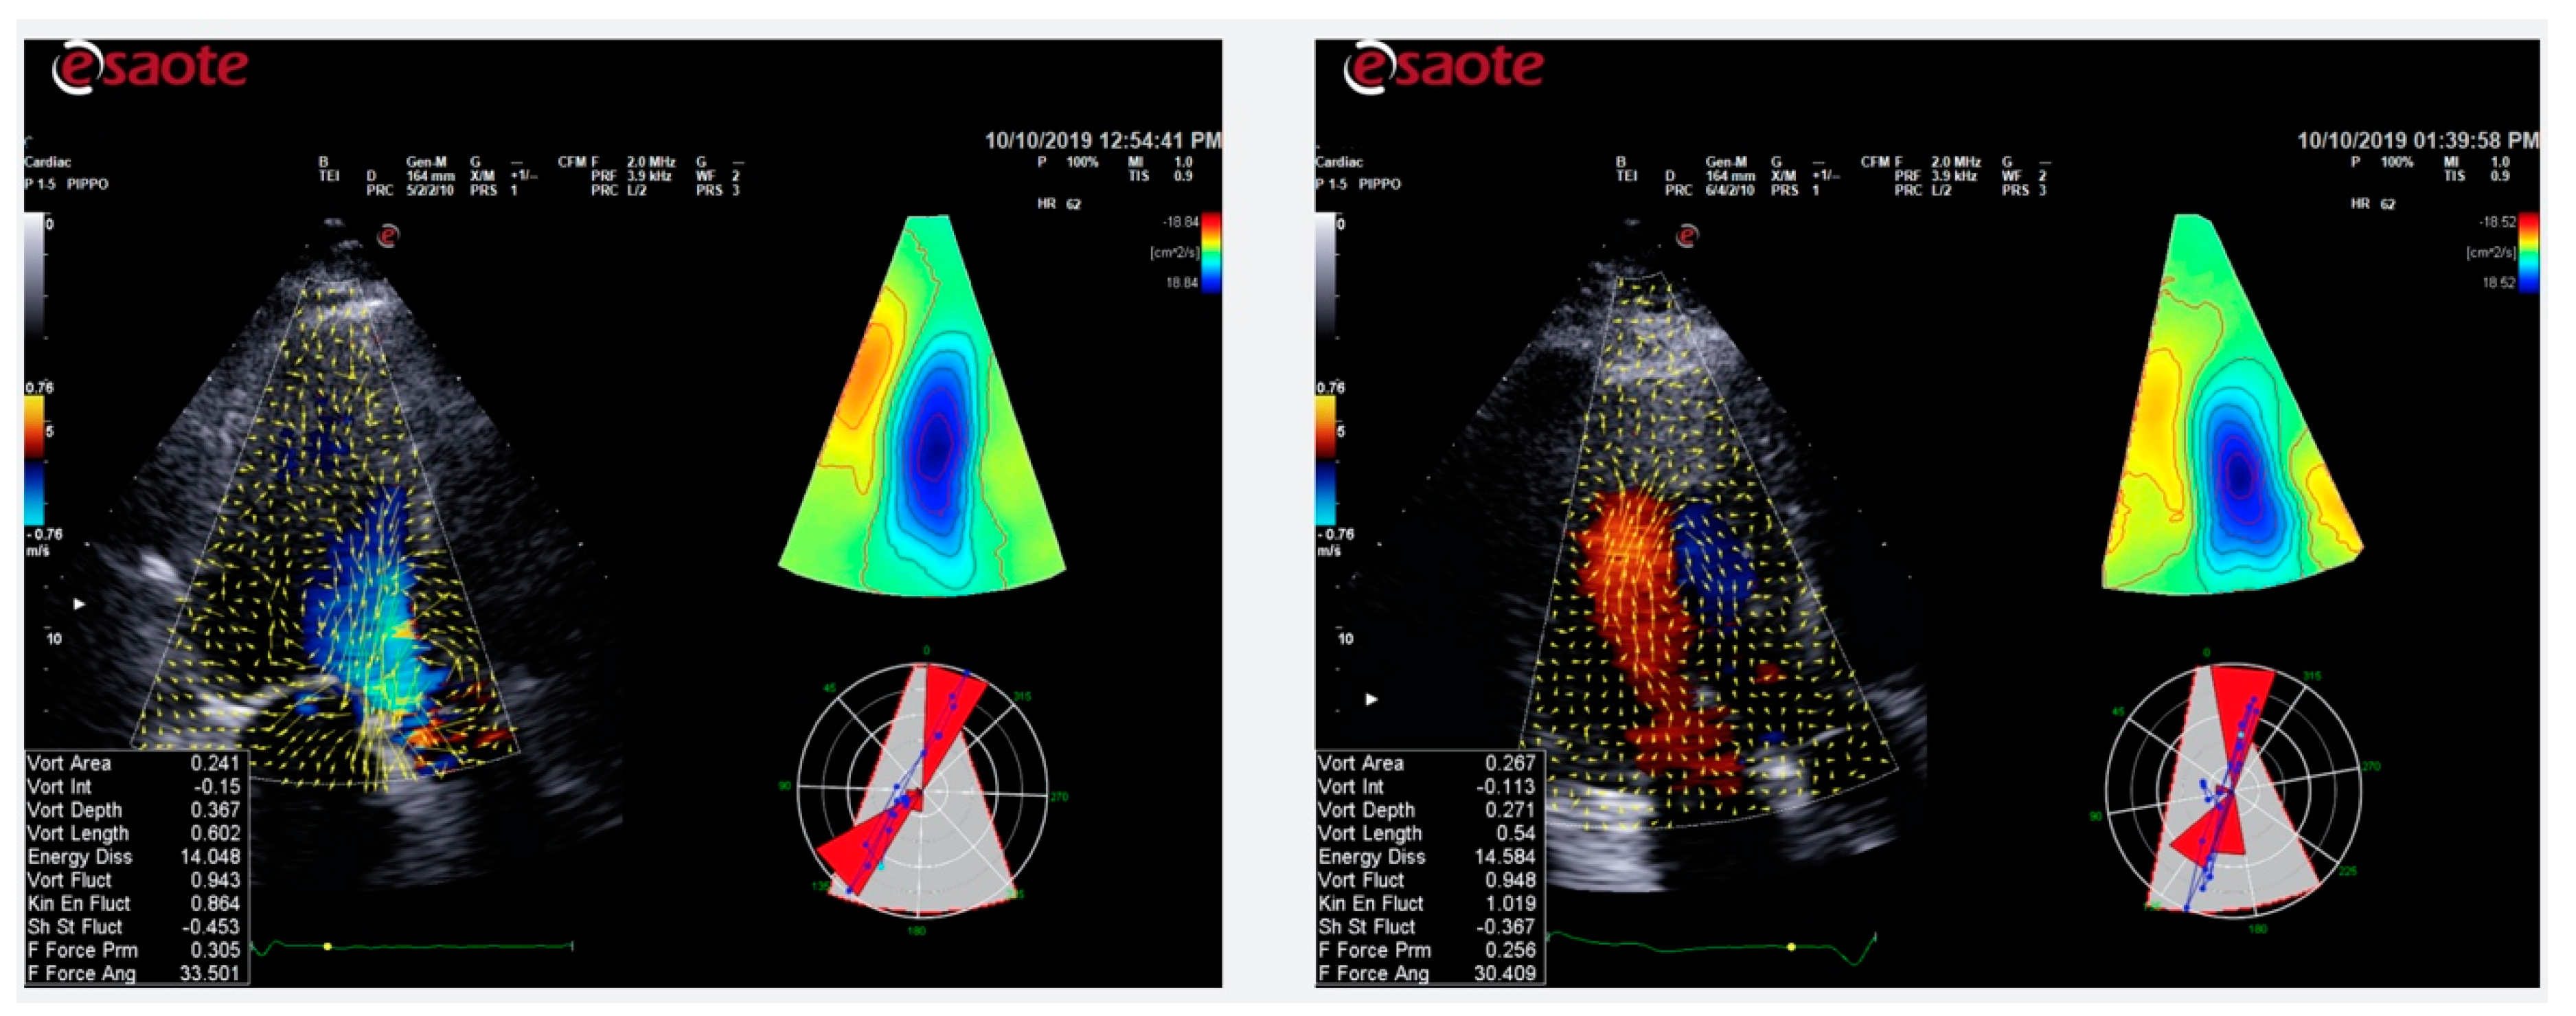

5. Color Doppler Flow Mapping

Role of CDFM in IHD

- Mele, D.; Smarrazzo, V.; Pedrizzetti, G.; Capasso, F.; Pepe, M.; Severino, S.; Luisi, G.A.; Maglione, M.; Ferrari, R. Intracardiac flow analysis: Techniques and potential clinical applications. J. Am. Soc. Echocardiogr. 2019, 32, 319–332. [Google Scholar] [CrossRef]

- Agati, L.; Cimino, S.; Tonti, G.; Cicogna, F.; Petronilli, V.; De Luca, L.; Iacoboni, C.; Pedrizzetti, G. Quantitative analysis of intraventricular blood flow dynamics by echocardiographic particle image velocimetry in patients with acute myocardial infarction at different stages of left ventricular dysfunction. Eur. Heart J.-Cardiovasc. Imaging 2014, 15, 1203–1212. [Google Scholar] [CrossRef] [PubMed]

- Chan, B.T.; Yeoh, H.K.; Liew, Y.M.; Dokos, S.; Al Abed, A.; Chee, K.H.; Aziz, Y.F.A.; Sridhar, G.S.; Chinna, K.; Lim, E. Quantitative analysis of intraventricular flow-energetics and vortex in ischaemic hearts. Coron. Artery Dis. 2018, 29, 316–324. [Google Scholar] [CrossRef] [PubMed]

- Nucifora, G.; Delgado, V.; Bertini, M.; Marsan, N.A.; Van De Veire, N.R.; Ng, A.C.T.; Siebelink, H.-M.J.; Schalij, M.J.; Holman, E.R.; Sengupta, P.P.; et al. Left ventricular muscle and fluid mechanics in acute myocardial infarction. Am. J. Cardiol. 2010, 106, 1404–1409. [Google Scholar] [CrossRef] [PubMed]

- Son, J.-W.; Park, W.-J.; Choi, J.-H.; Houle, H.; Vannan, M.A.; Hong, G.-R.; Chung, N. Abnormal left ventricular vortex flow patterns in association with left ventricular apical thrombus formation in patients with anterior myocardial infarction. Circ. J. 2012, 76, 2640–2646. [Google Scholar] [CrossRef] [PubMed]